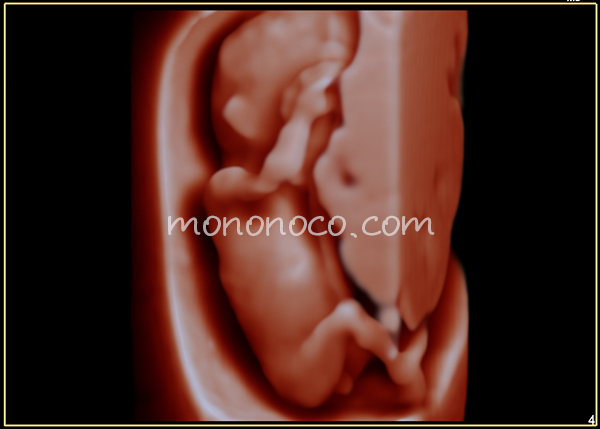

13週女児のベビーナブ

頂いた画像

横にしてみると確かに背骨に対して、突起がほぼ並行かも??

でも足曲げてるしなー。うーん…と考えた末、やはりよくわかりませんでした(笑)